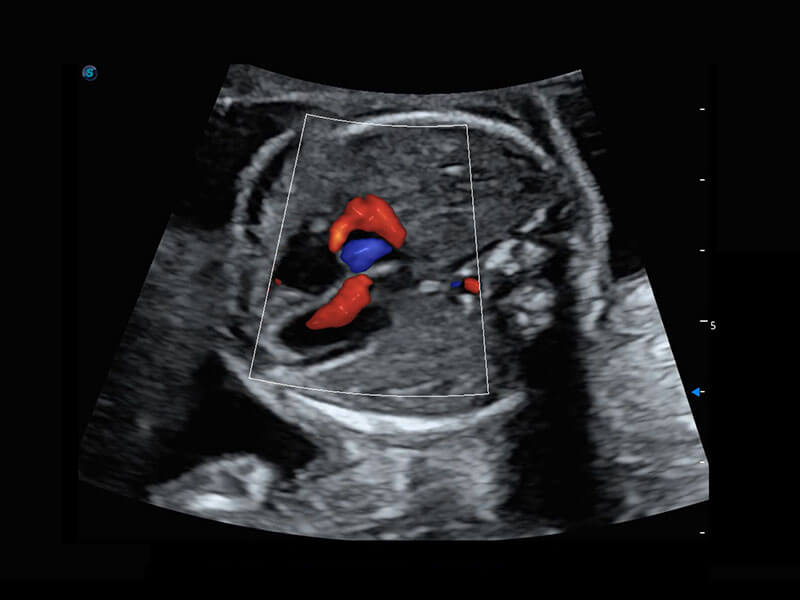

胎心筛查

P60搭载一系列胎儿心脏成像技术,实现更精细的胎儿心脏评估。

• 四腔切面

• 四腔心血流

• 右室双出口

• 胎心容积成像